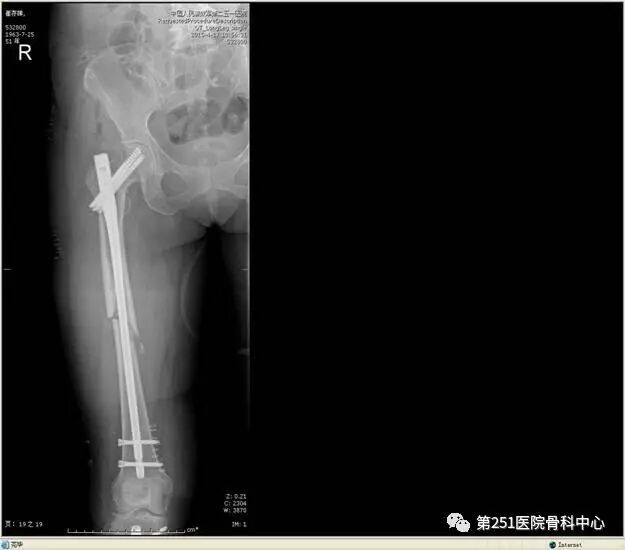

病例4:女性,车祸伤,同侧股骨、股骨颈合并胫腓骨骨折。

![]()